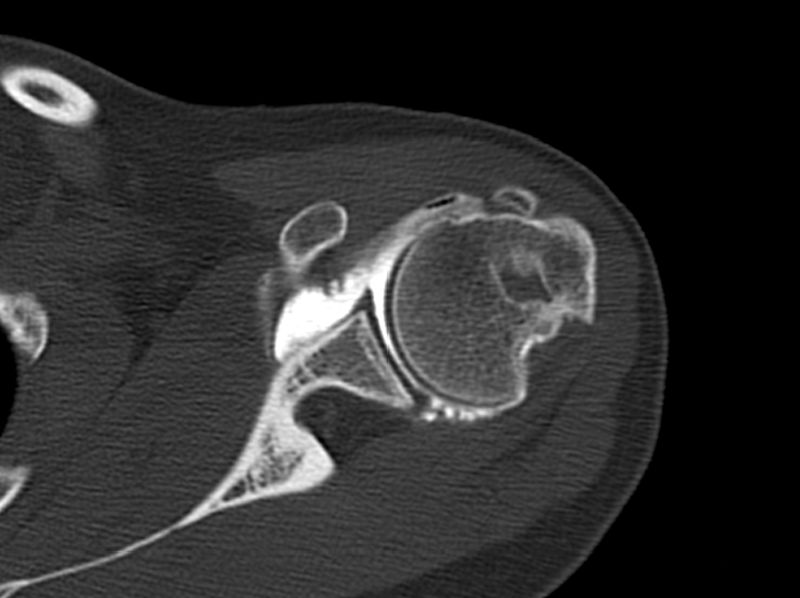

Axial computed tomography (CT) arthrogram view showing a large Malgaigne lesion.